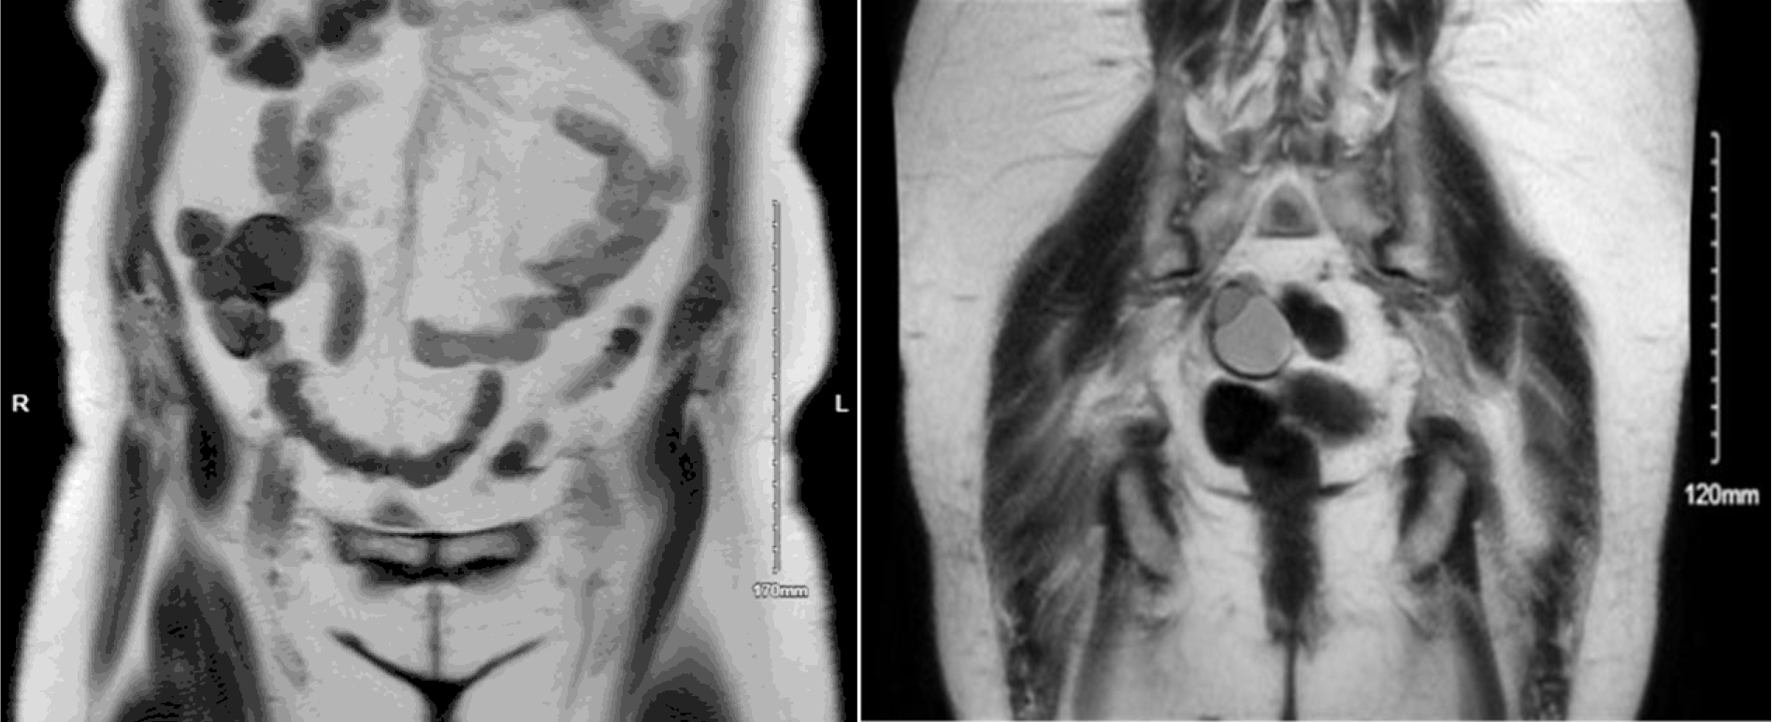

After this initial workup, her primary gynecologist referred her to a minimally invasive gynecology surgeon for further management. A colorectal surgeon was also consulted due to the cecal mass. After consultation with both surgeons, a plan for surgery was made. The patient was recommended to undergo a combined procedure of total abdominal hysterectomy, bilateral salpingo-oophorectomy, and excision of the pelvic mass, with colorectal surgery on hand for possible bowel resection with primary anastomosis. Given the uncertain origin of the omental mass, as well as the persistent presence of bilateral multicystic ovaries masses, preoperative tumor markers including a ROMA panel, carcinoembryonic antigen (CEA), and carbohydrate antigen 19-9 (CA 19-9) were obtained to aid in risk stratification and to help distinguish between gynecologic and gastrointestinal sources prior to surgical intervention. All results were within normal limits. A repeat CT scan of the abdomen and pelvis was recommended to assess if mass remained persistent prior to proceeding with surgery. The repeat CT scan (Fig. 2) showed a 4.0 × 5.8 × 7.2 cm mass in the right lower quadrant mesentery abutting the distal ileum and the cecum. It also redemonstrated cystic lesions in bilateral adnexa, right greater than left, that did not appear significantly increased in size from prior imaging.

Figure 2. Axial (a) and coronal (b) computed tomography (CT) images demonstrating an omental cystadenofibroma. The lesion appears as a well-circumscribed cystic mass within the anterior abdomen, consistent with a benign omental implant. The coronal view (b) provides a complementary perspective showing the lesion’s relationship to adjacent bowel loops and pelvic organs, further emphasizing its benign, non-infiltrative appearance.